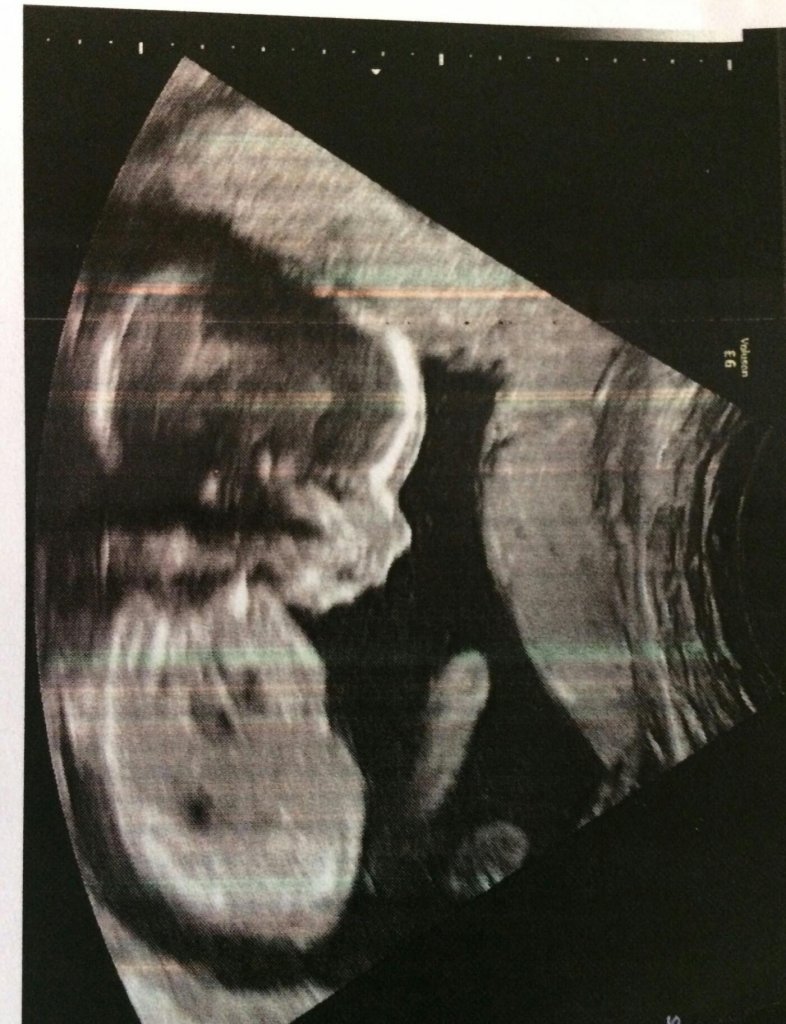

En ultraljudsbild florerar just nu på internet, efter att den gravida kvinnans bror delat den på de sociala medierna Imgur och Reddit.

Barnet på bilden skulle ha varit en liten flicka, men hennes morbror är, av allt döma, inte säker.

På bilden ser det ut som att barnet har en riktigt stor snopp.

Det är troligtvis flickans ena ben som ligger så att det ser ut som att hon är av välutrustat hankön.

Se den tankeväckande bilden här: